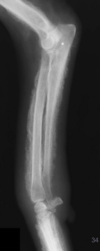

What is shown in this radiograph?

A

lateral bowing of distal femur and medial bowing of proximal tibia consistent with MPL

MPL; patella overlapping with femur rather than sitting in trochlear groove